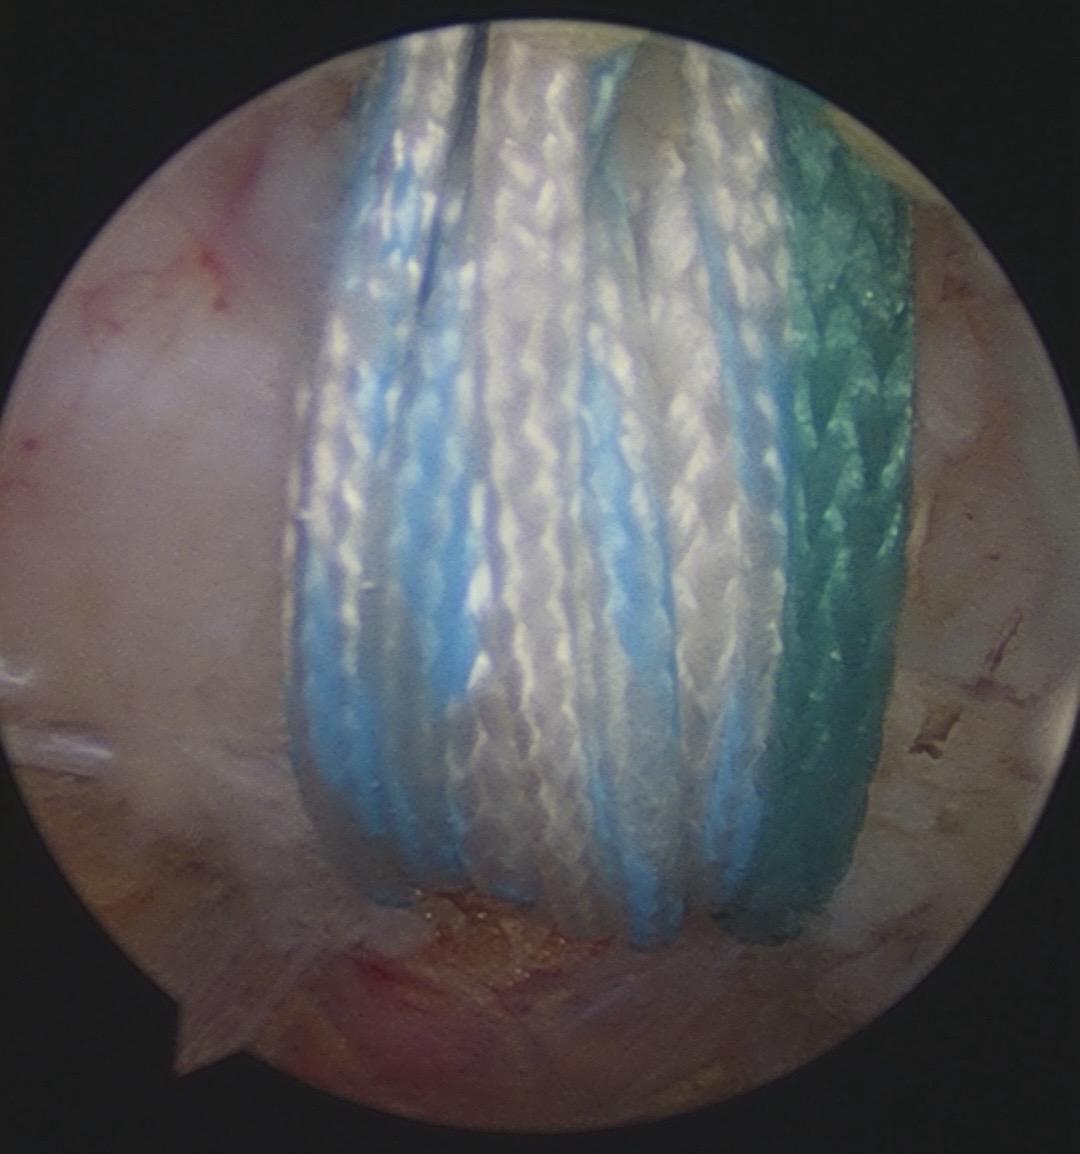

肩锁关节脱位。手术台上的每一次突破,都离不开前辈的倾囊相授。感谢赵立连主任的悉心指导,从理论到细节。